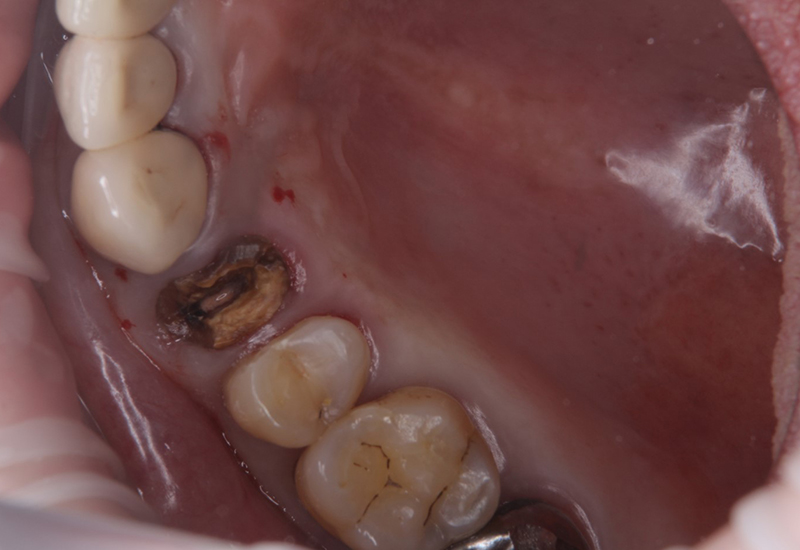

治療前 |

抜歯の画像です